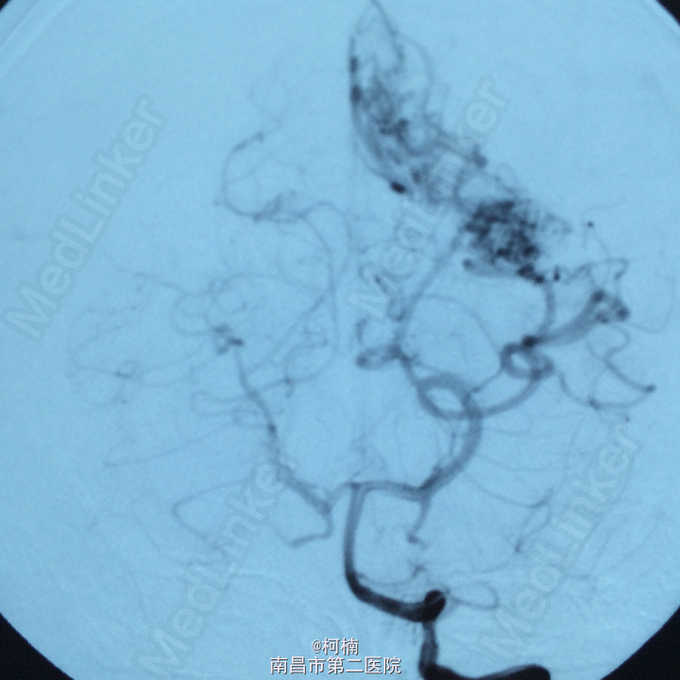

诊断:脑动静脉畸形 处理:予急诊行DSA检查,提示脑动静脉畸形,予行血管内栓栓塞治疗